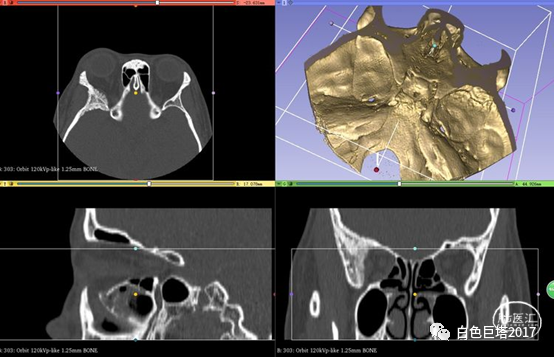

入院头颅CT检查提示右侧颞骨-眼眶后外侧壁骨质改变,眶内未见明显占位。报告考虑骨纤维异常增殖症可能性大。

3Dslicer重建可见眶后外侧壁骨质不均匀增厚,毛糙。

入院讨论病情,患者以突眼为主要症状,无眼球活动障碍,无炎性症状,无眶内占位,无甲状腺功能异常。结合患者入院头颅眼眶CT重建检查及既往MRI表现,考虑蝶骨嵴脑膜瘤可能,同时不能除外颅骨纤维异常增殖症。

蝶骨嵴内1/3脑膜瘤进展可出现眶上裂综合征(III、IV、VI颅神经及V-1受累)或Foster Kennedy综合征(同侧视神经萎缩,对侧视乳头水肿)。而本例考虑蝶骨嵴外1/3脑膜瘤,累及蝶骨大翼,眶后外侧壁及颞部骨质增生,眼眶缩小,眼球前突,眼睑肿胀。